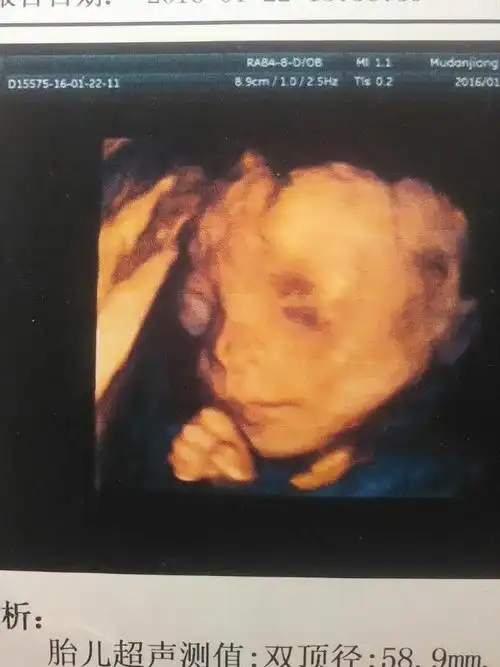

24周做的四维彩超,怎么宝宝拍出来的照片,这个样子啊,鼻子大,还有眼睛

各位妈妈们帮我看看四维照片,我家宝宝是睁着眼吗,那个黑色的是眼睛吧